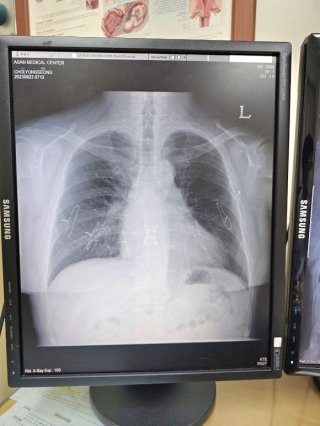

주요 증상과 진단

폐 섬유증의 증상은 매우 점진적으로 나타난다. 초기에는 운동 시 가벼운 숨가쁨 정도에 그치지만, 질환이 진행되면 계단 몇 칸만 올라가도 숨이 차고 일상 활동이 힘들어진다. 밤에는 마른기침이 지속돼 수면의 질이 떨어지고, 만성 피로감이 동반된다.

산소 교환이 원활하지 않으면 손끝이나 입술이 푸르게 변하는 청색증이 나타나기도 하며, 말기에는 산소통 없이는 생활이 어려워진다. 폐 섬유증은 폐에 국한된 질환이 아니다. 만성 저산소 상태가 지속되면 심장이 이를 보완하기 위해 과도하게 작동하면서 폐동맥 고혈압이나 우심부전 같은 심혈관 합병증으로 이어질 수 있다.